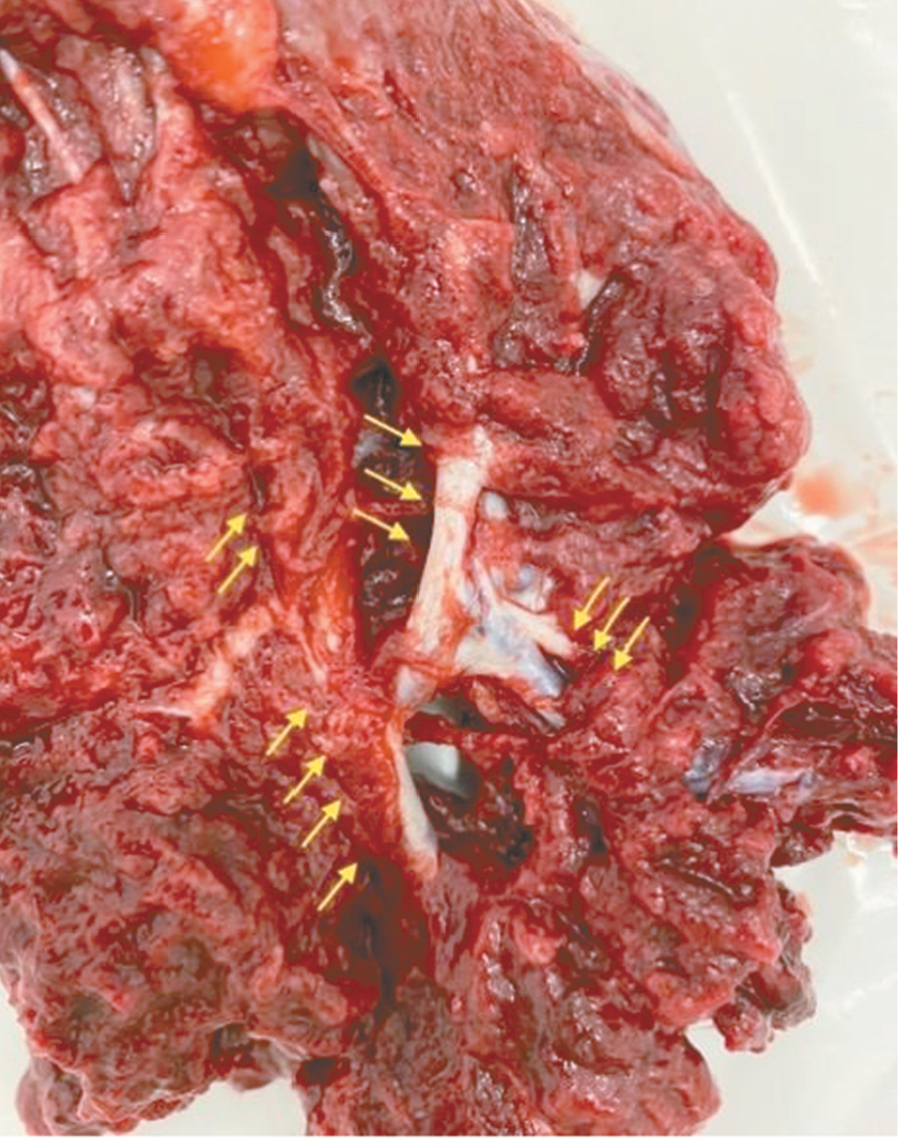

Является ли симптом «обнаженного сосуда» патогномоничным для параметральной инвазии или нет, еще предстоит выяснить; однако в ходе исследования установлена его связь с частотой гистерэктомий в группах с наличием симптома «обнаженного сосуда», что, вероятно, обусловлено мощной сосудистой сетью коллатералей и неоангиогенезом. Во всех случаях обнаружения данного признака впоследствии была выполнена вынужденная гистерэктомия (рис. 3–6, пациентка Н., 37 лет).

Рис. 3. Макропрепарат плаценты при врастании в параметрий (стрелками указаны мощные сосудистые структуры)

Рис. 4. Макропрепарат матки с врастанием плаценты в параметрий (стрелками указаны мощные сосудистые структуры)